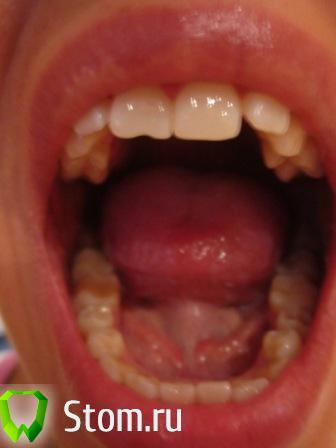

oxpod Опубликовано 2 мая, 2012 Поделиться Опубликовано 2 мая, 2012 (изменено) Здравствуйте, нужна помощь разобраться в ходе лечения.. Проблема такая: самое главное что меня беспокоит - это гипертонус мышц челюсти, рук и ног (примерно 2 года). С детства я дышала ртом, рот был постоянно открыт, сформировался открытый прикус. Позже я научилась насильно держать рот закрытым. Также всю свою жизнь я скриплю зубами во сне. Недавно заметила (месяца три назад), что щелкает правый сустав.Была на консультациях у нескольких ортодонтов, неврологов, сомнолога, лора. Заключение лора - искривление носовой перегородки - буду делать септопластику. Со стороны невролога - гипертонус, присутствует ротовое дыхание, остановок дыхания во сне нет (делали диагностику). Отправили на МРТ шейного отдела, пока не делала. 1 ортодонт. по результатам КТ нижняя чюлюсть находится в положении подвывиха, слева головка НЧ расположена выше на 5 мм, вестибулярнее и мезальнее центра, справа - ниже, дистальнее и кнутри, деструктивные изменения, расстояние до центра - от ветви НЧ слева 105 мм, справа 115 мм. Со стороны шейного отдела - суст. отросток Dens Т2 ротирован против часовой стрелки, наклонен и смещен влево. План лечения : нормализация черепно-челюстной системы- устранение подвывиха НЧ и установка ее в оптимальное равновесие. Применение Тенс-монитора, изготовление окклюзионной каппы Ортотик. Устранение гиперонуса у остеопата, удаление 18 28 38 48, пластика мягких тканей рта, вестибуло- и френуло-пластики для устранения рецессии, горизонтальной резорбции костной ткани альвеолярных отростков. Ортодонтическое лечение - нормализация окклюзии, устранение деформации зубных рядов, пожизненная ретенция, пл-ка с защитой для языка на ночь.Диагноз: нейтральная окклюзия 1 класс по Энглю вертикальная резцовая дизокклюзия правосторонняя, узкий апикальный базис верхней и нижней челюсти макроденти фронтальных и боковых зубов, смещение центральной линии, укороченная уздечка верхней губы и нижней губы, дисфункция мышц языка макроглоссия затрудненное носовое дыхание, нарушение осанки, дисфункция ВНЧС 2. Нашла в нашем городе другую клинику, где применяют Тенс и ортотик, была на консультации у профессора, он сначала отправил меня к лору (где выяснилось искривление перегородки), к неврологу-сомнологу (где выяснилось что дыхание во сне в норме). Сказал что лечение предыдущего ортодонта неправильное, так нельзя начинать лечение без расчета по ТРГ. Отправил меня к своим ортодонтам(их у него в клинике два), предварительно сделав ТРГ, а сам уехал на месяц. Сказал что если по расчету ТРГ у меня прикус завышен, ортотик мне применять нельзя. Первый его ортодонт сказала что нужно удалять восьмерки и ставить брекеты. И сказала что у меня инфантильное глотание. Вторая сказала удалять пятерки и ставить брекеты. Что делать с суставами и гипертонусом мне так и осталось не ясно. Вопрос в том, что хотелось бы знать правильный план лечения, с чего нужно начать, в какой момент подключить остеопата, нужен ли мне тенс монитор и ортотик или нужен другой способ установки челюсти в правильное положение. Как я понимаю брекеты ставить сразу смысла нет, станет еще хуже? Заранее спасибо всем откликнувшимся, фото улыбки прилагаю, второе фото с начала - расслабленное положение рта, первое и второе фото ОПТГ (делала месяц назад) , последнее - в октябре 2011 г. Фото сжала, так как с изначальным размером не прикреплялось.с уважением! Изменено 2 мая, 2012 пользователем oxpod Ссылка на комментарий